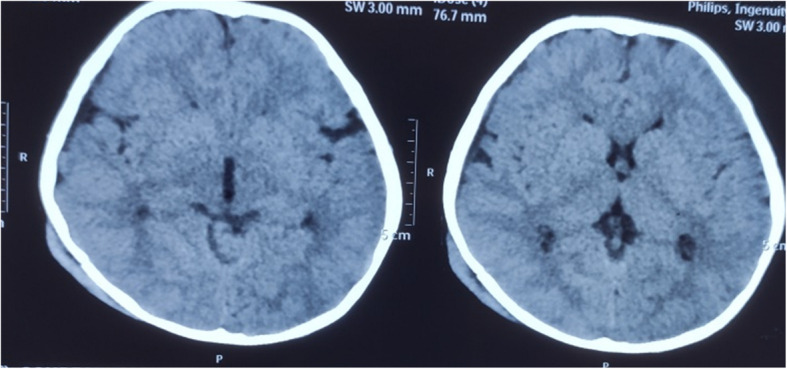

Case presentation: A 3 years old male with recent history of traumatic head injury following road traffic accident presented with weakness of left upper and lower limbs. On diagnostic evaluation there was right sided basal ganglia acute infarct. On further investigations basal ganglia infarct was secondary to moya moya disease. Patient was managed conservatively with single low dose anti platelets therapy, anti epileptic and was discharged with good functional outcome.